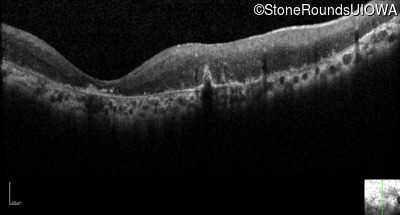

Optical Coherence Tomography - Right - Light Perception

Exemplar